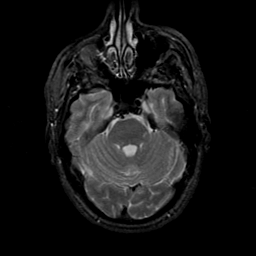

MR Study #21, November 3, 1991 -- Slice #14